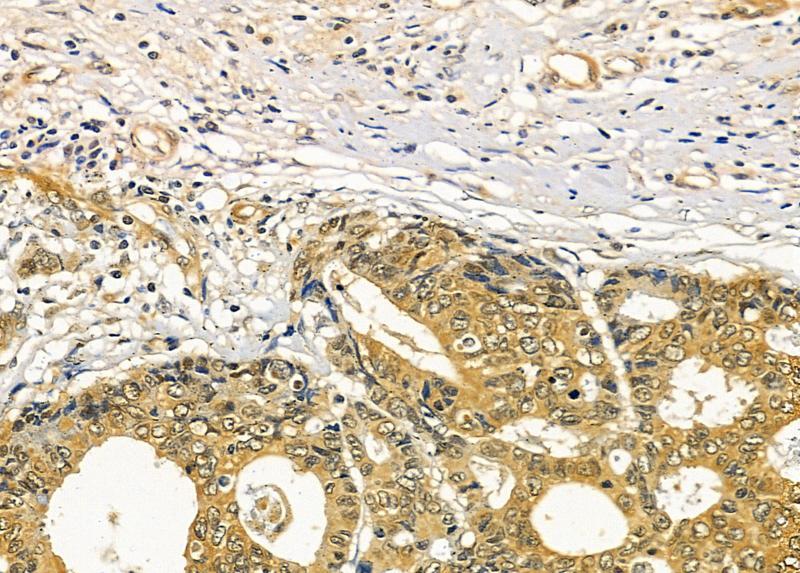

Supportive validation

- Submitted by

- Invitrogen Antibodies (provider)

- Main image

- Experimental details

- Immunohistochemistry analysis of RASA4 in human prostate cancer and para-carcinoma tissue. The sample was formaldehyde fixed and a heat mediated antigen retrieval step in citrate buffer was performed. Samples were incubated with RASA4 polyclonal antibody (Product # PA5-115826) using a dilution of 1:100 (4°C overnight) followed by HRP conjugated anti-Rabbit secondary antibody.